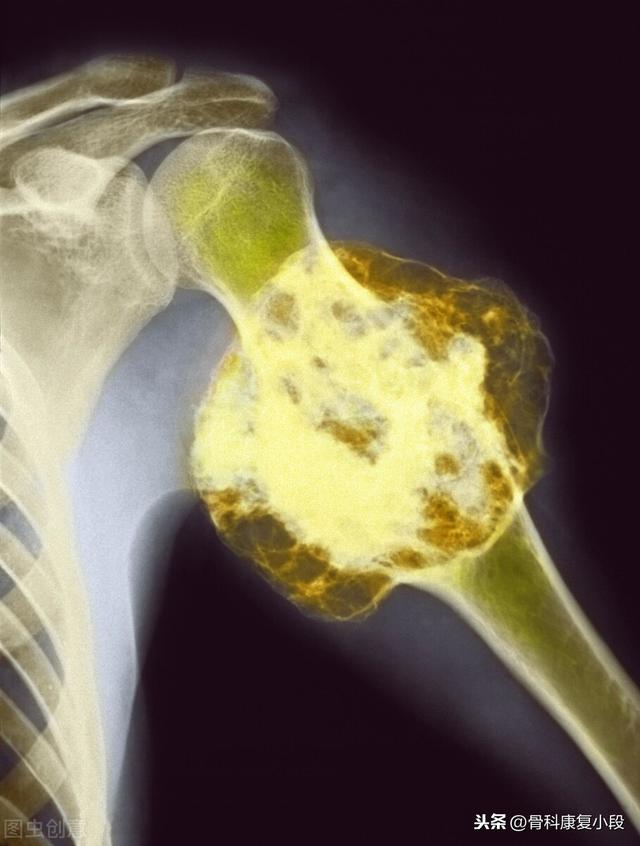

この症例は58歳のゲイ男性で、肩を軽く伸ばしただけで痛みが続くようになり、X線検査で低密度病巣が見つかった:

これは骨転移に基づく軽微な外力による病的骨折であった。穿刺が行われ、病理結果は低分化肺腺癌の骨転移であった。

左肺にあるこの不規則な結節が原発巣で、わずか2.6cmしかない。このような骨転移を伴う肺がんは、もはや手術不可能です。肺がんはあまりにもありふれた病気であり、初期症状の中には非典型的なものや無症状のものさえあるからだ。肺がんの約30%では、転移の症状が最初の症状であり、さらなる肺がんが発見される前に転移が最初に発見される。

骨転移で起こる症状にはどのようなものがありますか?最初の症状は痛みです。骨転移を起こした部位は骨が破壊されるために痛みを感じますが、最初ははっきりした症状がなかったり、断続的な痛みだったりしますが、腫瘍が正常な骨をどんどん破壊して徐々に悪くなっていくため、転移部位の痛みも徐々に悪くなっていきます。臨床的には、体のある部分の骨の痛みで、悪性腫瘍の骨転移という症例に出くわすことがあります。以前、ある症例に出会ったのですが、40歳で、肩が痛く、五十肩かと思い、薬用オイルを数日揉んでも改善が見られず、ますます痛みが強くなったので、病院で検査をしたところ、MRIを撮ったところ、肩甲骨が(腫瘍の)かけらに食べられており、骨転移を考え、胸部CTを撮ったところ、右肺に結節があり、生検をして病理検査をしたところ、肺がんの骨転移でした。その内容は以下の通りである。

骨転移部位では、正常な骨組織が破壊され腫瘍組織に置き換わり、腫瘍細胞は常に増殖しているため、多くの骨転移部位で軟部組織の腫瘤影が見られ、腫瘤が表在する部位であれば触知することができる。また、腫瘍組織による正常な骨組織の侵食は、正常な骨構造の破壊と脆弱化につながるため、正常な外力下でも骨折が生じることがあり、病的骨折と呼ばれます(下図)。脊椎への転移は、疼痛や病的骨折に加えて、脊髄神経根の圧迫を伴い、感覚障害、筋力低下、場合によっては高カルシウム血症などの症状を呈することもあります。